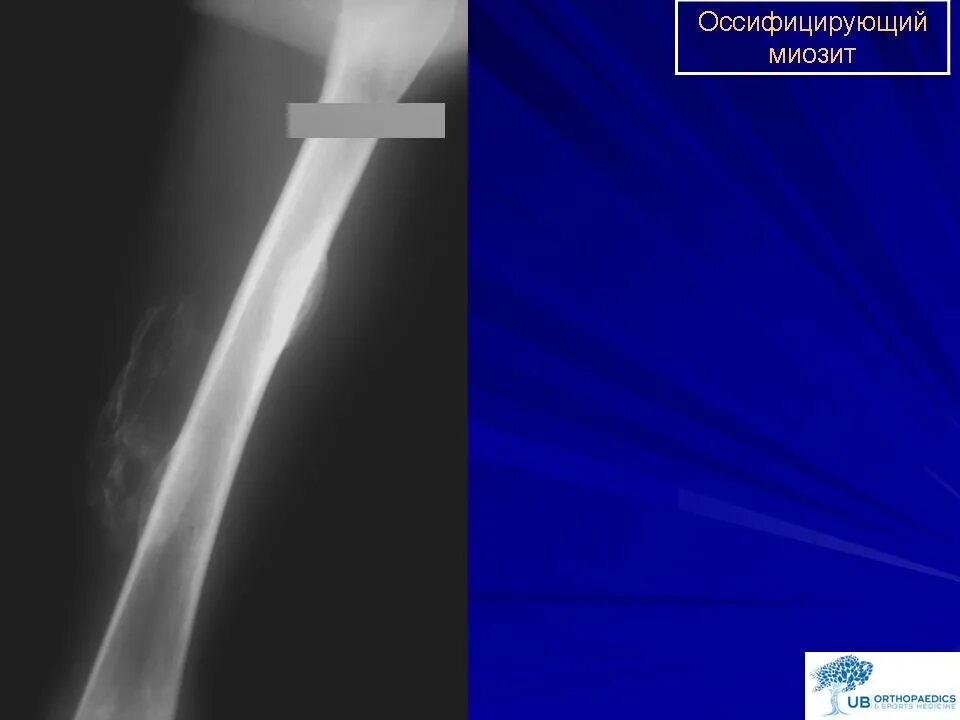

Оссифицированный миозит